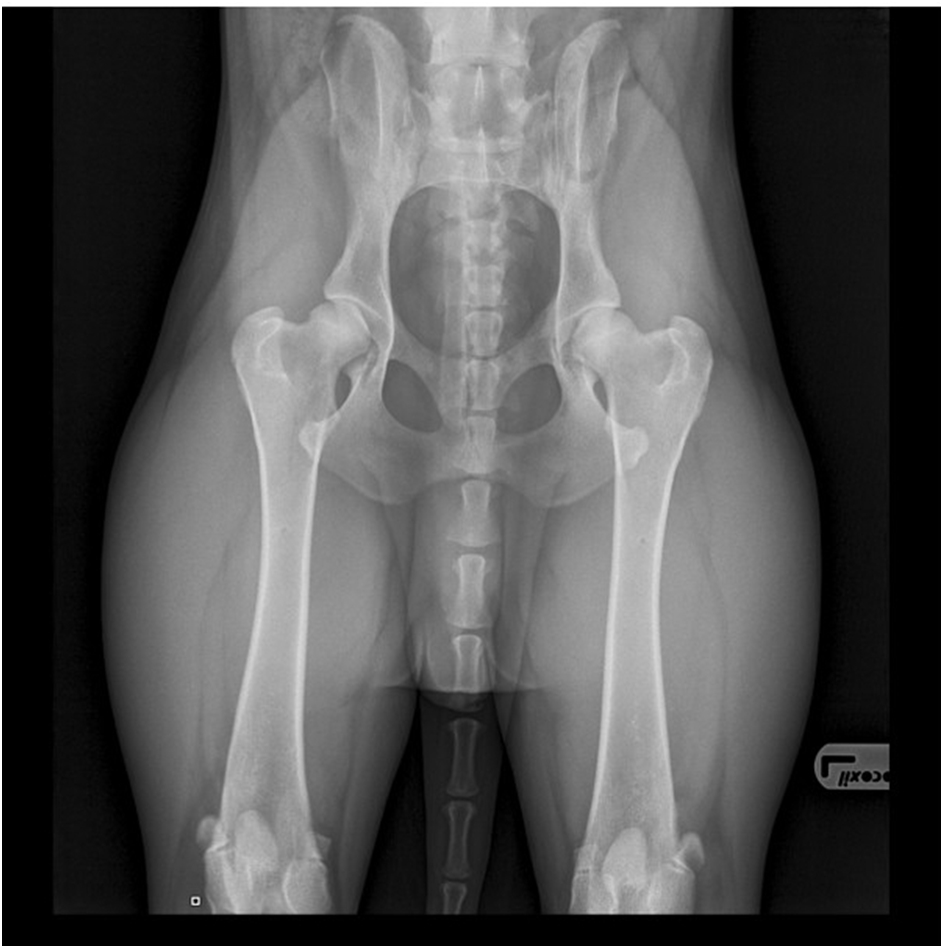

Das Hüftgelenk des Hundes besteht aus einem Hüftkopf und einer Hüftpfanne, die richtig zusammenpassen müssen. Das Röntgenbild unten zeigt ein normales Hüftgelenk (HD A) des Dobermanns.

Wenn Hüftkopf und Hüftpfanne nicht richtig zusammenpassen, liegt eine Hüftdysplasie vor, d. h. das Hüftgelenk ist dann nicht richtig ausgebildet. Bei einer Hüftdysplasie ist der Abstand zwischen Kopf und Pfanne zu groß, was zu Arthrose (Gelenkverschleiß) führt. Der Knorpel verliert an Qualität, die Gelenkschleimhaut entzündet sich (Arthritis) und um das Gelenk herum kommt es zum Knochenumbau. Diese Osteoarthritis verursacht auch Schmerzen. Unten sehen Sie eine Röntgenaufnahme der Hüfte eines Dobermanns mit schwerer Hüftdysplasie, insbesondere am rechten Hüftgelenk (HD E).

Normale Hüfte

Schwere Hüftdysplasie rechts